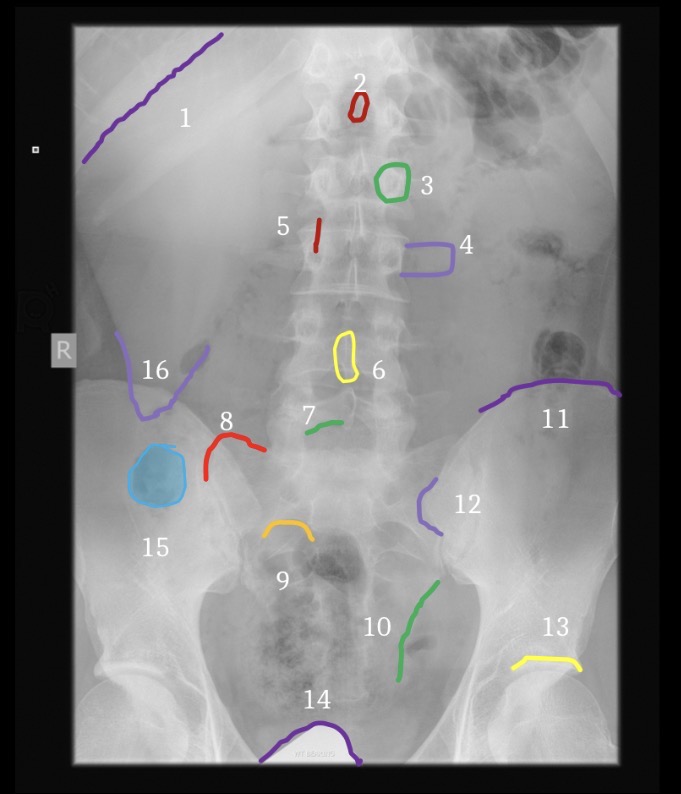

1

Brest

3

Fat deep to abdominal muscle

5

Gluteal crease

6

Lateral margin left psoas muscle

7

Hemidiaphragm

8

Gastric air bubble